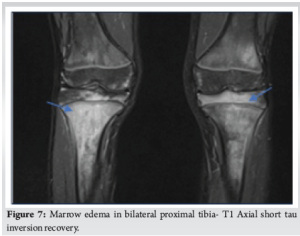

A 13-year-old boy presented to the outpatient department with a 5-month history of bilateral knee, hip and ankle pain. The pain was predominantly over the hips and radiating to the thighs. Pain was acute in onset, gradually progressive, and described as a dull ache and relieved by medication. No constitutional symptoms were present, and he was able to do his daily activities. His birth history, developmental milestones, and immunization records were normal. His older sister had a history of Juvenile Idiopathic oligoarthritis. His clinical examination was normal. Laboratory investigations such as ESR (46 mm/h), CRP (0.9), uric acid (5.1 mg/dL) were normal, and the Mantoux test was negative. HLA B27 and RF test were also negative. Blood culture showed no growth. His X-ray radiographs were normal. MRI pelvis with hip, thigh, and clavicle screening was done (Fig. 1-7), which showed altered signal intensities involving the bilateral acetabulum, pubic bones, iliac bone, right femur, bilateral tibia, and clavicle, along with diffuse periosteal thickening involving the left iliac wing. Bone marrow biopsy was also done to rule out any hematological malignancy – showed trilineage hematopoiesis with erythroid hyperplasia. No blast cells were noted.

CRMO is a recurrent autoinflammatory nonbacterial osteomyelitis characterized by lytic, sclerotic and hyperostotic bone lesions [3]. Despite the chronicity character, CRMO often exhibits periodic flares and phases of remission. It often affects children and adolescents, with a female-to-male ratio of 2:1 [5]. The pathogenesis of CRMO remains unclear and may be linked to an imbalance between pro-inflammatory cytokines (Interleukin [IL]-6, IL-1, tumor necrosis factor alpha) and anti-inflammatory cytokines (IL-10). These cytokines are involved in bone resumption and remodeling through osteoblasts and osteoclasts activation [5]. A consistent feature of CRMO is the gradual onset of pain, accompanied by swelling and tenderness over the affected bones. Patients commonly present in many clinical forms, from unifocal or multifocal lesions with a relapsing and remitting course. Symptoms include fever, pain, swelling, and a limited range of motion in the affected region [6]. Metaphysis of long tubular bones such as the femur, tibia, clavicula are commonly affected, followed by the spine and pelvis. Clavicle, mandible, and sternum are the typically affected sites [7]. The clavicle and mandible are the classical locations of involvement. It is the most common disease to affect the medial end of the clavicle, similar to our case. Nevertheless, a unifocal unusual location in the absence of trauma should prompt suspicion for CRMO [4,8]. A subset of patients also present with comorbidities affecting other systems, including the skin, gastrointestinal tract or joints [9]. Radiological findings are nonspecific. Plain radiographs are frequently unremarkable. On MRI, active disease shows oedematous marrow changes [8,10]. Active disease in the clavicle is characterized by lytic destruction of the medullary bone in the medial aspect. A lamellated periosteal reaction is often seen, although sequestra are not formed. At this stage, MRI typically reveals a mass involving the clavicular marrow, cortex, and periosteal new bone formation. MRI shows homogeneous T1 hypointense and T2 hyperintense images [8]. The role of biopsy is controversial since histological features are nonspecific but it may help to exclude infectious osteomyelitis and malignant bone tumors [11]. An accurate diagnosis is often challenging due to a lack of specific clinical findings, laboratory tests, and radiology. Therefore, CRMO remains a diagnosis of exclusion [12]. Two diagnostic criteria, the Jansson criteria and Bristol criteria, have been proposed (Tables 1 and 2). The clavicle is an unusual location for infectious osteomyelitis and is therefore very specific for inflammatory lesions, such that unifocal clavicular lesions are considered positive in the Bristol criteria [3].